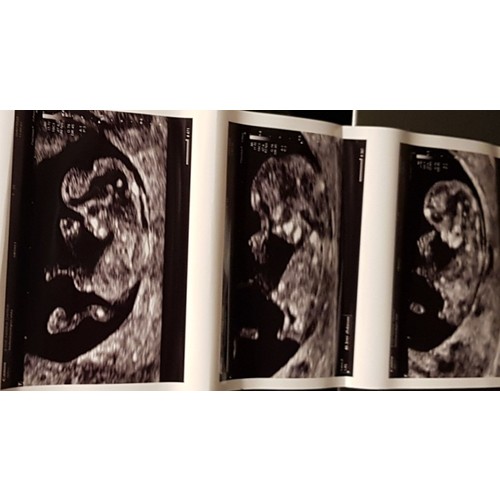

Nou dames.... ik kan er niets van maken 😅 jullie misschien wel 🤣

Sorry haha ik zie het ook niet, maar wel geinig: die voetjes!

Lijkt jongetje

Ziet iemand hier iets?

Weet iemand of je hier de nub op zie en wat het evt dan voorspelt

Nub kun je op deze foto niet zien, heb je nog een ander plaatje?